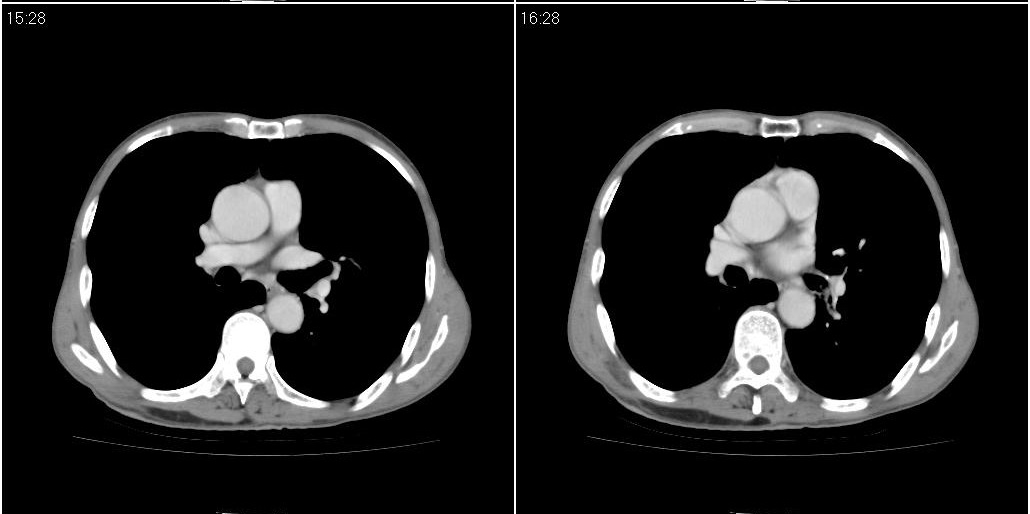

1)右肺中叶慢性炎症并支气管扩张,节段性肺不张。2)两肺下叶支气管扩张。

1)右肺中叶慢性炎症并支气管扩张,节段性肺不张。2)左肺下叶支气管扩张